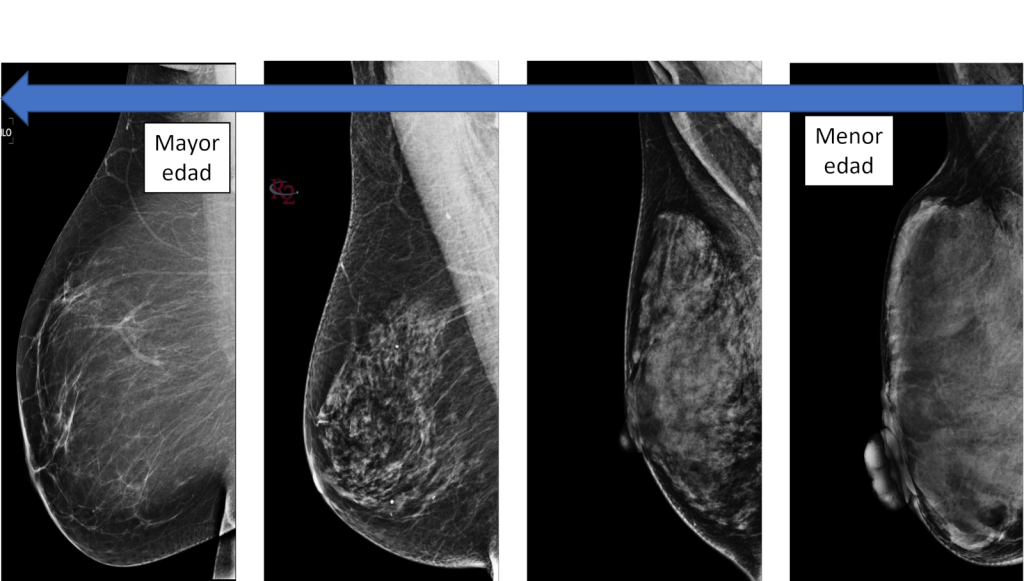

En general, la mama densa es mayor en pacientes jóvenes y va disminuyendo con la edad.